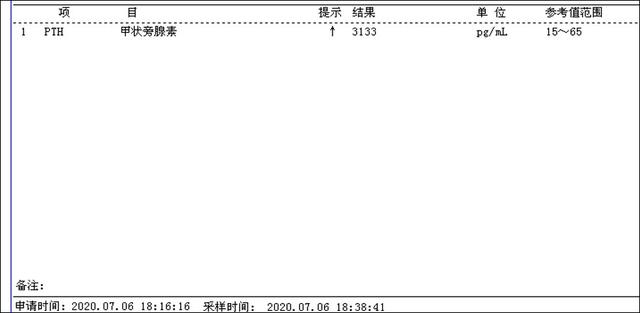

治疗前甲状腺旁腺素非常高(3300pg/ml),血钙正常,超声显示双侧甲状腺旁腺明显增大(如下图),核素扫描显示甲状旁腺功能亢进性骨代谢异常性骨病(骨骼变形)。